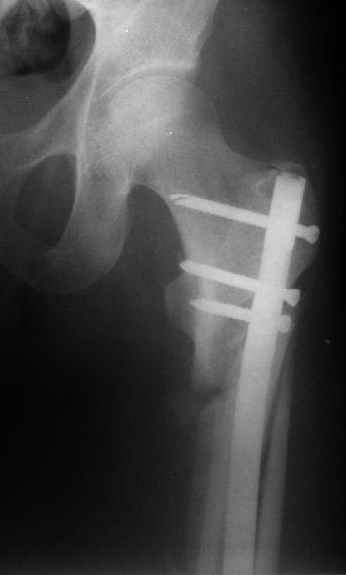

Когда открыто убрали DHS встали перед выбором, что ставить? Так, как это был подвертельный перелом - поперечная линия на уровне малого вертела то поставили обычный бедренный гвозь и один прокс блокирующий винт, который затянули компрессирующей заглушкой.

К сожалению под рукой только одна картинка от этой операции.

Я пошел на операцию имея стерильным и обычный бедренный гвоздь ChM и реконструктивный.